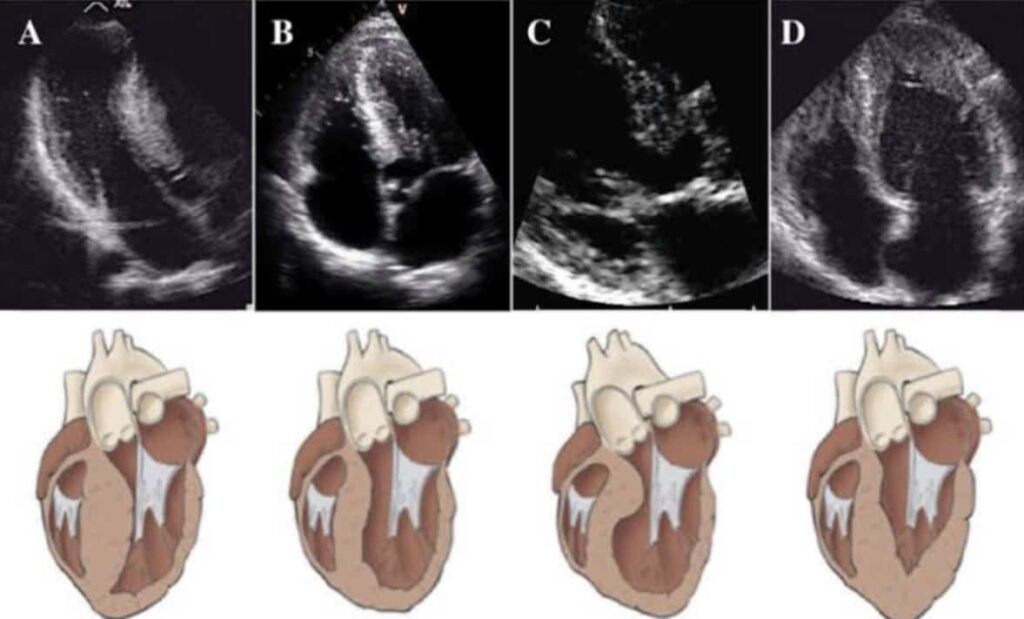

Podemos classificar a Miocardiopatia Hipertrófica (MCH) como a forma com a qual ela vai se apresentar (Fenótipo), e os sintomas e riscos relacionados a doença estão muito relacionados aos diferentes tipos.

Fenótipo Obstrutivo: Obstrução dinâmica da via de saída do ventrículo esquerdo (Mais comum).

Fenótipo Não Obstrutivo: Hipertrofia sem obstrução significativa.

Outro modo de classificação ou distinção, é relacionado a forma de apresentação anatômica, ou seja, qual a principal ou principais partes do coração estão hipertrofiadas.

Variantes anatômicas: Hipertrofia septal, apical, global ou localizada.

Na suspeita clínica, podemos utilizar o Ecocardiograma Transtorácico: Método padrão-ouro inicial, identifica espessamento septal, funcionamento de valvas, quando de sangue cabe no coração, como ele é empurrado, medidas de pressão.